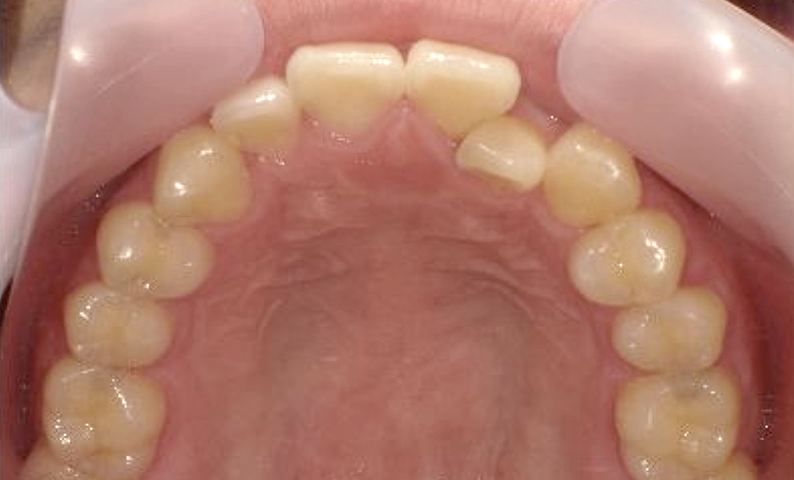

症例_025 上顎だけの部分矯正

治療期間:7ヶ月金額:30万円+税女性前歯のガタガタ上の前歯だけ

| Before | After |